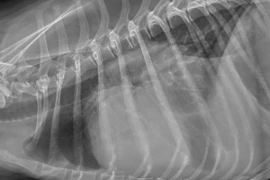

Auffrischungskurs für Strahlenschutzbeauftragte 09-2024